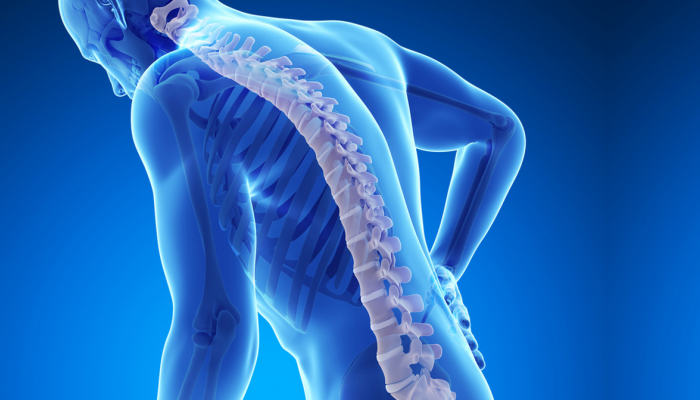

أليك أهم اعراض غضروف القطنية

ما لا تعرفه عن الام القطنية؟

علاج الفقرات القطنية اسفل الظهر